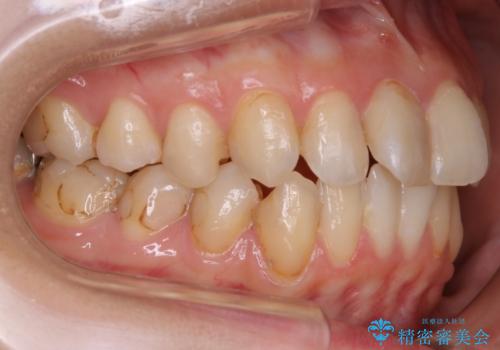

当院では矯正治療を主訴にご来院された方は治療開始前に必ず精密検査を受けていただきます。

ご本人は症状もなくご自覚がなくても実は歯周病が進行していたり、根管治療が必要な歯が見つかるということもあります。

基本的にはそういった歯周病・虫歯に対しての治療は矯正治療開始前に完治させておく必要があります。これは、矯正装置装着後は清掃不良になりやすく虫歯の進行が早まったり、歯を移動させることで歯周病や根尖病巣が悪化する恐れがあるためです。